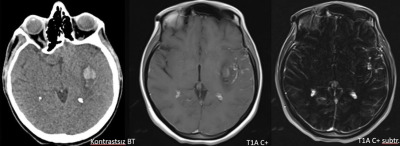

- Kontrastsız BT görüntülemede (E) bu düzeyde intraparankimal kanama ile uyumlu hiperdens alan gözleniyor (ok).

- Kontrastlı T1A görüntüde (C) ve kontrastlı T1A çıkarma görüntüde (D) medialde bulunan alanda kontrastlanma izlenmezken (ok), lateralde bulunan boyutça daha küçük alanda kontrastlanma izleniyor (ok). Ayrıca anevrizma komşuğunda silvian fissürde leptomeningeal kontrastlanma görülüyor.